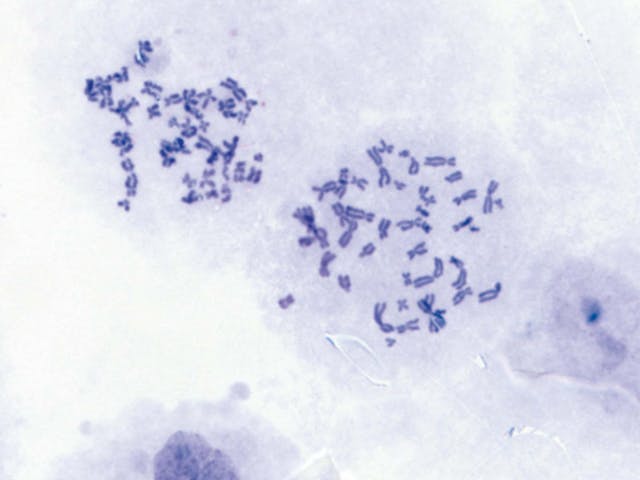

組織學標本(人) 染色體標本(人)

染色體標本(人) 腎組織(人)